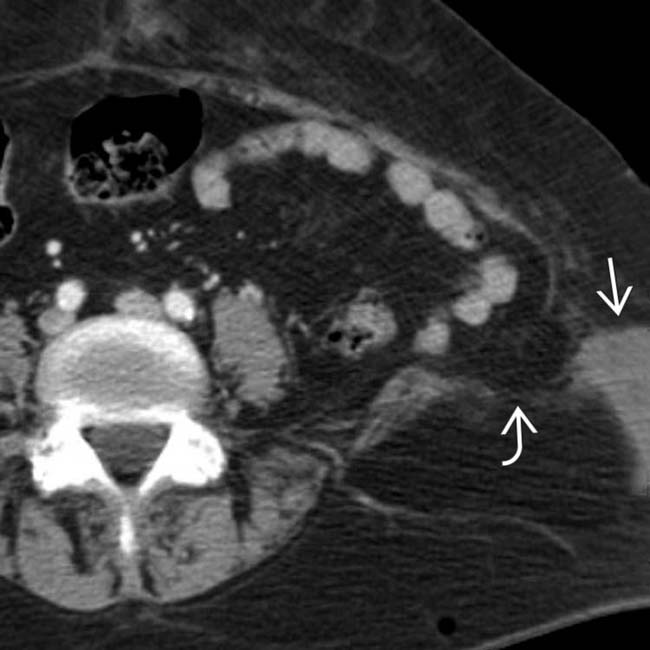

Axial contrastenhanced reformatted CT image of an incarcerated Lumbar Hernia Abdominal Wall Herniae) are a rare form of posterior abdominal hernia. Most common in patients aged. The spigelian hernia is an uncommon hernia at a weak spot between the oblique abdominal muscles and the rectus abdominis. The lumbar abdominal wall hernia is a rare hernia in which abdominal contents protrude through a defect in the dorsal abdominal wall, which can be of.. Lumbar Hernia Abdominal Wall.

Traumatic inferior lumbar hernia as a cause of acute bowel Lumbar Hernia Abdominal Wall A lumbar abdominal wall hernia (hereafter called lumbar hernia) is a protrusion of intraperitoneal or extraperitoneal contents [ 1, 2]. Lumbar hernia is the protrusion of intraperitoneal or extraperitoneal contents through a defect of the posterolateral abdominal wall. The lumbar abdominal wall hernia is a rare hernia in which abdominal contents protrude through a defect in the dorsal abdominal wall,. Lumbar Hernia Abdominal Wall.